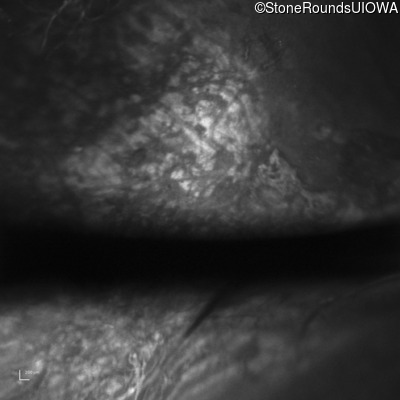

Infrared Fundus Photograph - Right - 20/200 sc

Exemplar